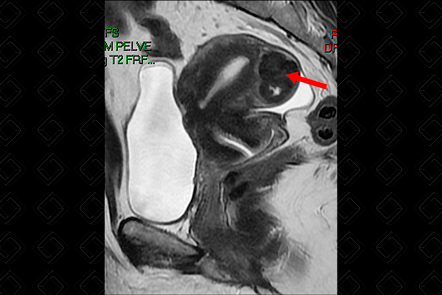

Descrição das figuras 1, 2, 3 e 4: Ressonância magnética da pelve feminina. Imagens pesadas em T2 nos planos axial e sagital (A = bexiga; B = útero; C = reto). Útero em retroversão, de contorno lobulado e sinal heterogêneo, por conta de nódulos miometriais, bem delimitados, hipointensos em T2, compatíveis com leiomiomas, destacando-se:

• Transmural, corporal posterior, medindo 5,0 x 4,8 x 4,6 cm (setas vermelhas à direita);

• Subseroso, corporal lateral direito, medindo 3,0 x 2,0 x 1,8 cm (setas vermelhas à esquerda).